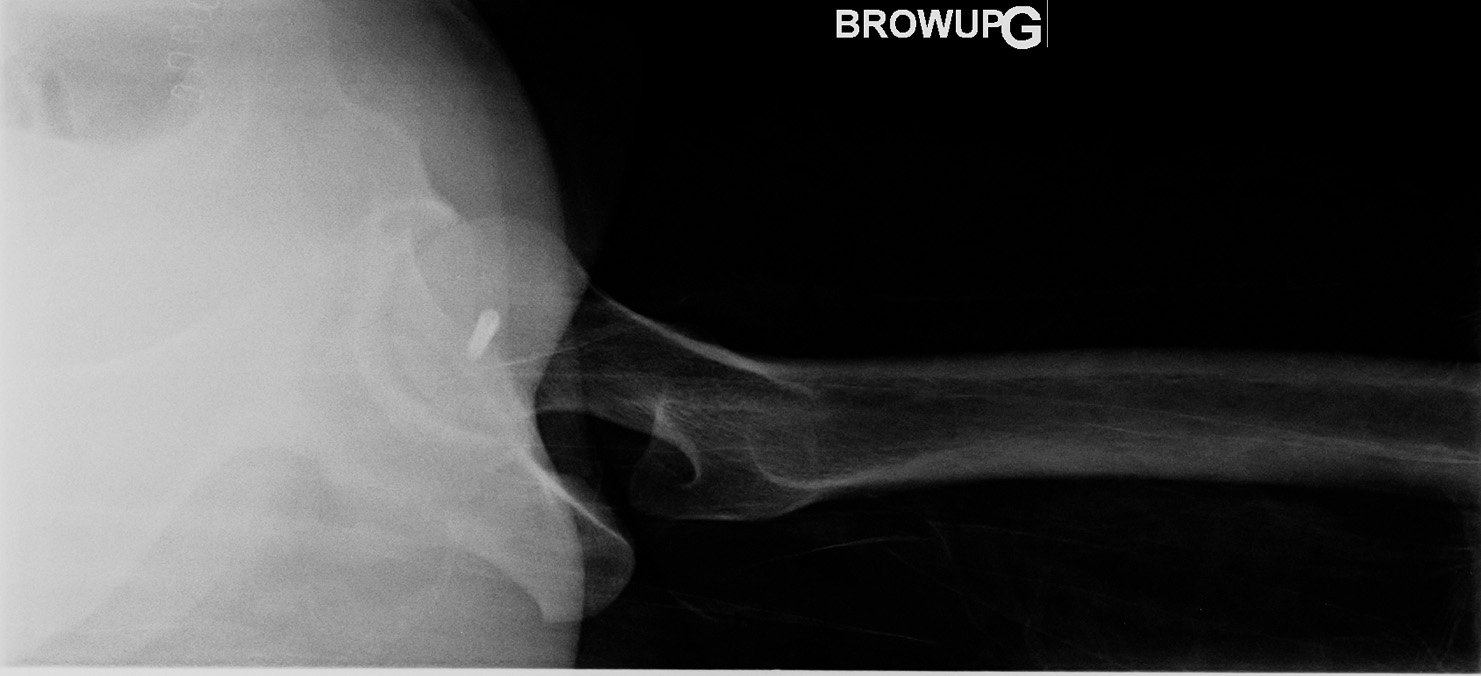

16-year-old female:

Postoperative control of a fracture-dislocation of the femoral head.

Femoral head fracture

Post reduction status of a femoral head fracture-dislocation with screw fixation of the bone fragment.